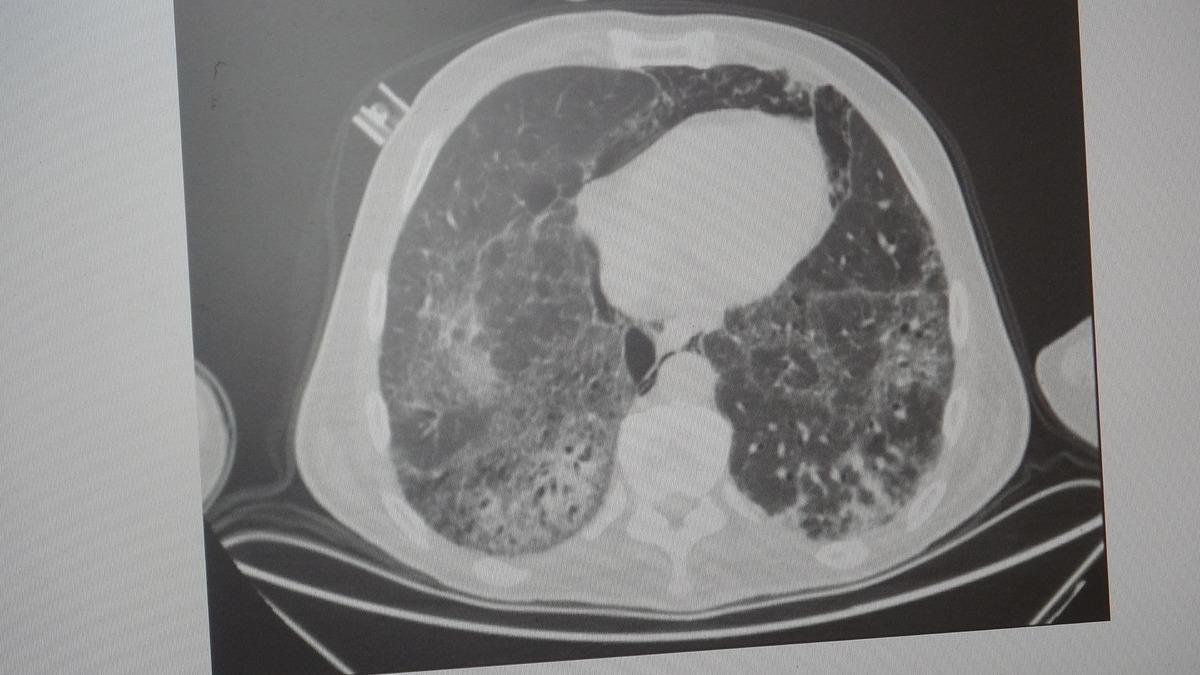

KOAH, zararlı maddelerin akciğeri parçalamasıyla oluşan bir rahatsızlık ve bunun da en önemli nedeni sigara.

KOAH’ın akciğer dokusunu tahrip eden bir hastalık olduğunu ve bu nedenle de hastaların enfeksiyona açık hale geldiğine dikkat çeken Karakurt, "Akciğer dokusunun tahrip olduğu her durumda hastaların enfeksiyona karşı eğilimi artar ve enfeksiyona yakalandıkları zaman bunun geçmesi güç olur. KOAH'lı hastalar zatürre geçirdikleri zaman öksürük ve balgam artışı gibi bir takım belirtiler gelişir. Ayrıca ateşin 38,5 derecenin üstüne çıkması, nefes darlığının artması, titremeyle birlikte ateşin yükselmesi ve bir takım bilinç bozukluğu gibi belirtiler hastanın zatürre olduğunu gösterebilir. Bu nedenle hastaların erkenden doktora başvurmaları önemlidir" dedi.